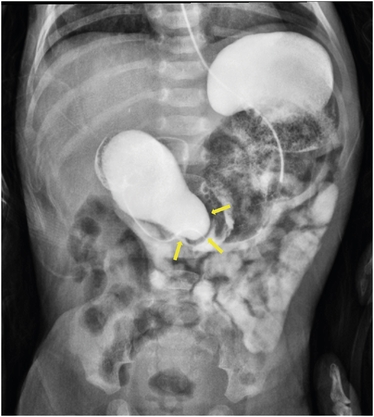

Abdominal bloating and vomiting resolved immediately after the procedure, and a regular diet was initiated the day after the intervention. Subsequent upper gastrointestinal imaging revealed no signs of intestinal obstruction or passage disturbance (Fig. 3). During the 3-month follow-up period, the patient exhibited no recurrence of symptoms and displayed normal growth.

Fig. 3

Following upper gastrointestinal series no longer reveals a dilated duodenum and passage disturbance.